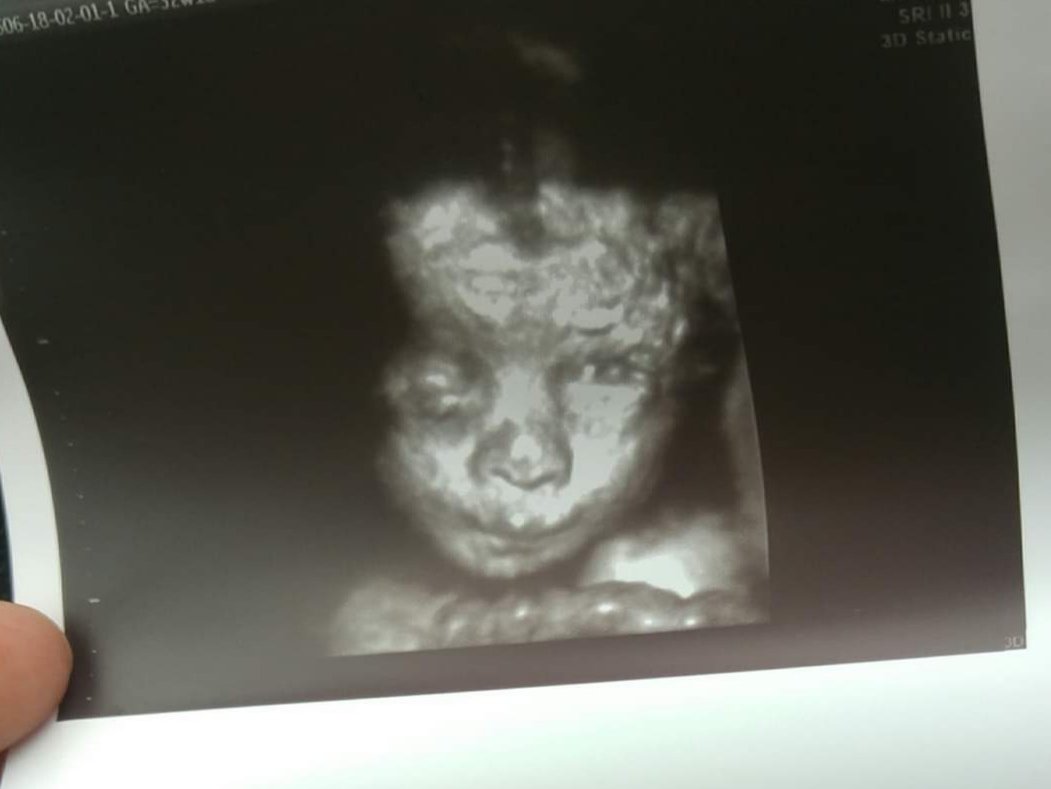

Ale fasolka i calkiem inaczej to wyglada w 3 d. Ja mojego aniołka tez mam. W 3d praktycznie pozniej lekarz po pomiarach robił 3d zeby miec pamiątki. Pozniej dzieciaczki wyglądają słodko. I powiem. Szczerze ze identycznie po porodzie Zobacz załącznik 1062419